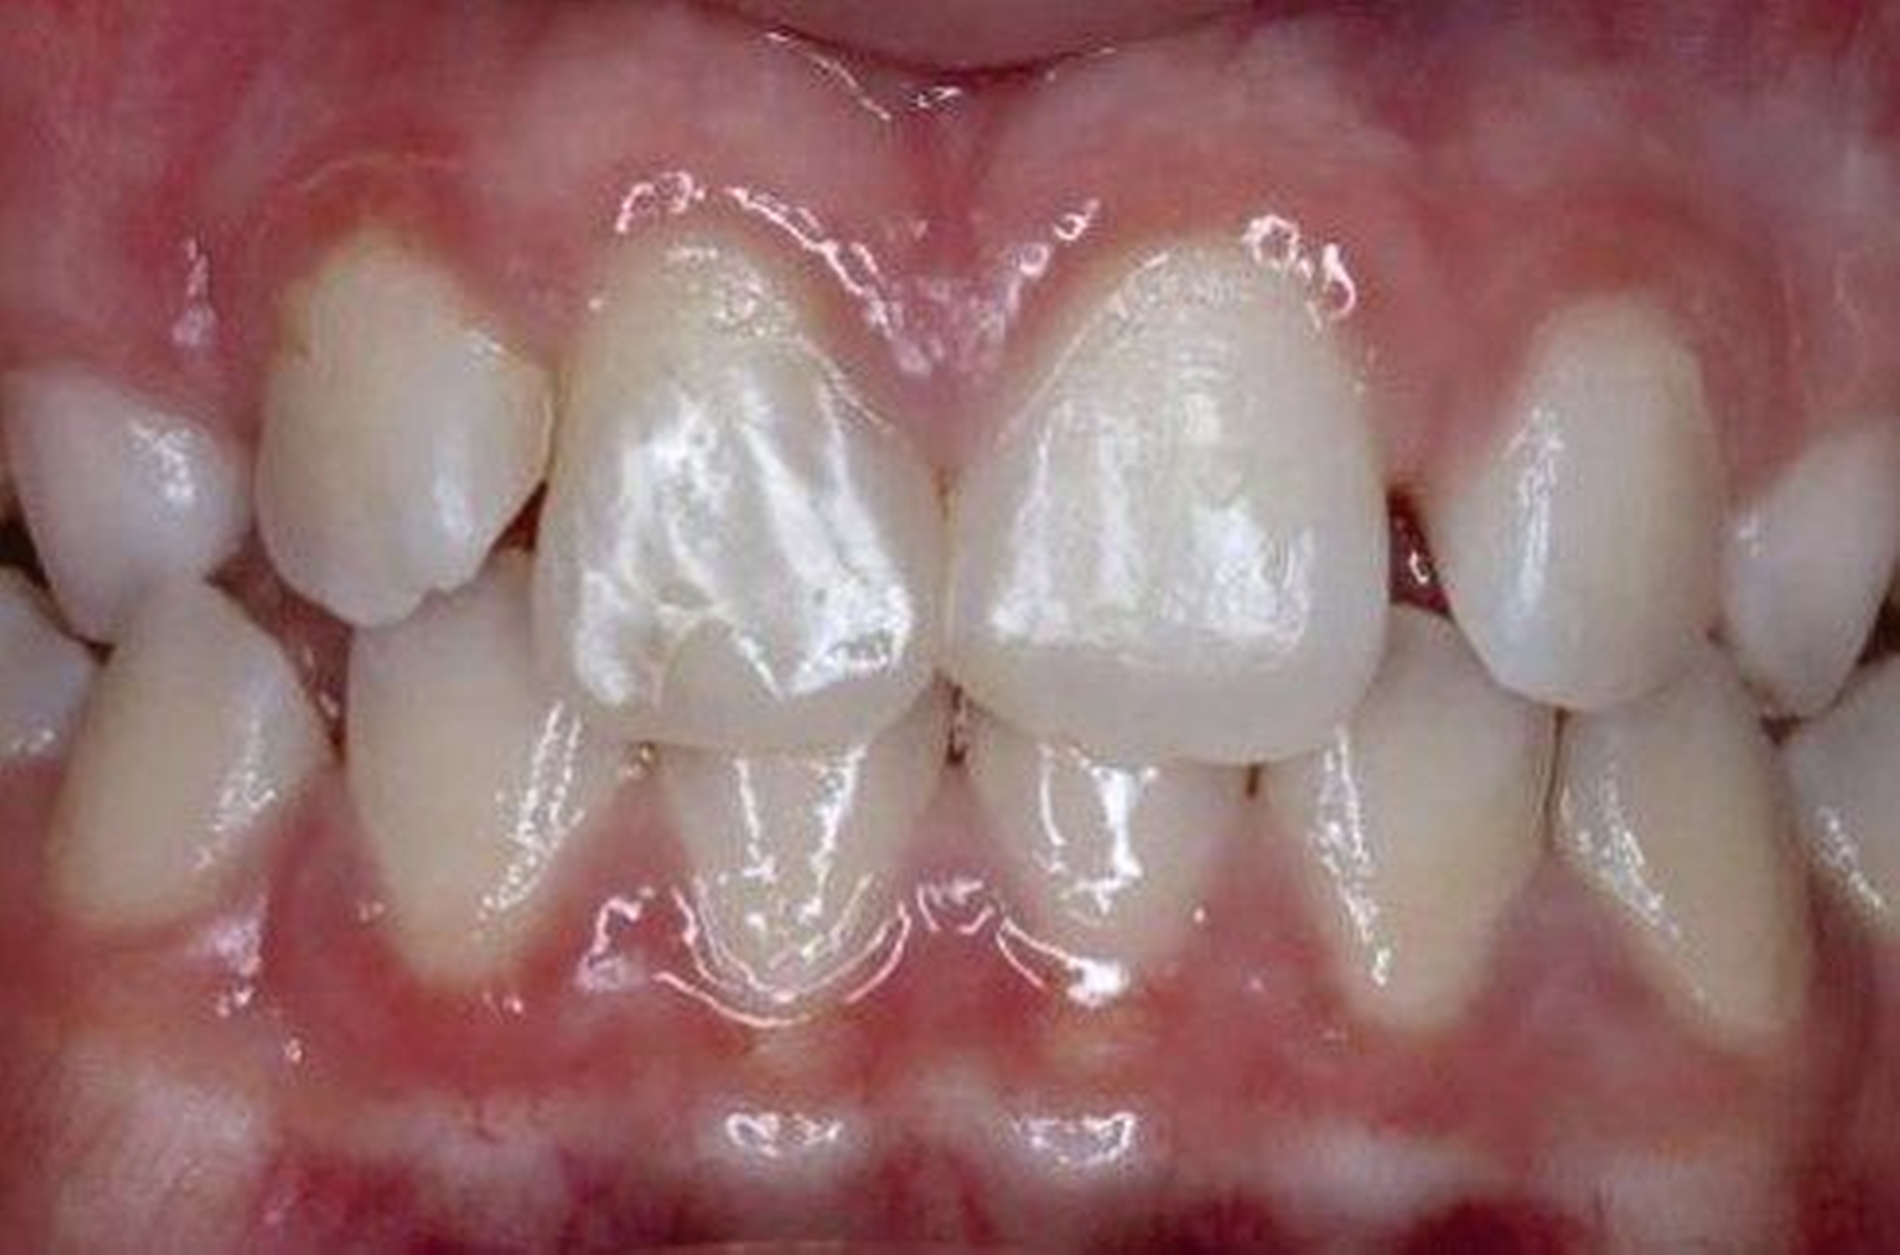

Eine Dekoronation ist eine chirurgische Intervention, die durchgeführt werden kann, wenn aufgrund ausgeprägter Schädigungen der desmodontalen Zellen und der Wurzeloberfläche eine Resorption auftritt. Im Rahmen der klinischen Untersuchung imponiert der betroffene Zahn aufgrund der Ankylose mit einem metallischen (hellen) Klopfschall. Röntgenologisch lassen sich Resorptionslakunen an der Wurzeloberfläche erkennen. Bei progressiver Resorption und Infraposition des betroffenen Zahnes in Relation zur Restdentition kann eine Dekoronation indiziert sein [Malmgren et al., 2015] (Abbildung 2).

Das Ziel der Dekoronation ist es, die klinische Krone unter Belassung der resorbierenden Wurzel zu entfernen, damit der Alveolarknochen aufgrund der Knochenneubildung bei Ersatzresorption erhalten und eine optimale Voraussetzung für spätere Interventionen gegeben werden kann [Malmgren et al., 2006]. Bei Patienten im Wachstum kann die Dekoronation eine sinnvolle Therapieoption darstellen, um den teils erheblichen Knochenverlust in Verbindung mit der chirurgischen Entfernung der ankylosierten Zahnwurzel zu vermeiden (Empfehlung 60).